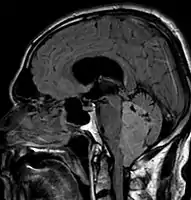

Ependymoma of 4.ventricle in MRI.

Ependymoma of 4.ventricle in MRI. Left without, right with contrast-enhancement.